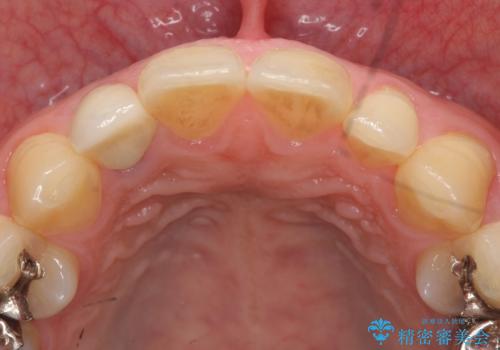

- 金属を使っていない被せ物に替えたいといらっしゃった方の症例です。

再根管治療終了後、オールセラミッククラウンによる補綴を行いました。

今回用いたオールセラミッククラウンはジルコニアフレームという白い素材の上にセラミックを盛っているため、審美性が非常に高いのが特徴です。

また、ジルコニアは人工ダイヤモンドの材料にも使われているほど高い強度を持っており、そのためオールセラミッククラウンは審美性だけでなく、奥歯やブリッジの補綴も可能とするクラウンです。